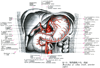

人体局所解剖図譜 II巻